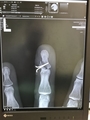

肩と手のレントゲンを取って診察待ち。様子を見に会社の子も来てくれたので安心です。

で、診断結果。右肩脱臼、左中指末端の開放骨折、同薬指が手のひらの中で骨折。

中指は関節部分で割れており、傷口が開放状態なので、要手術。

経皮ピンニングという手法で、直径1mm程度のステンレスピン2本で骨片を固定。